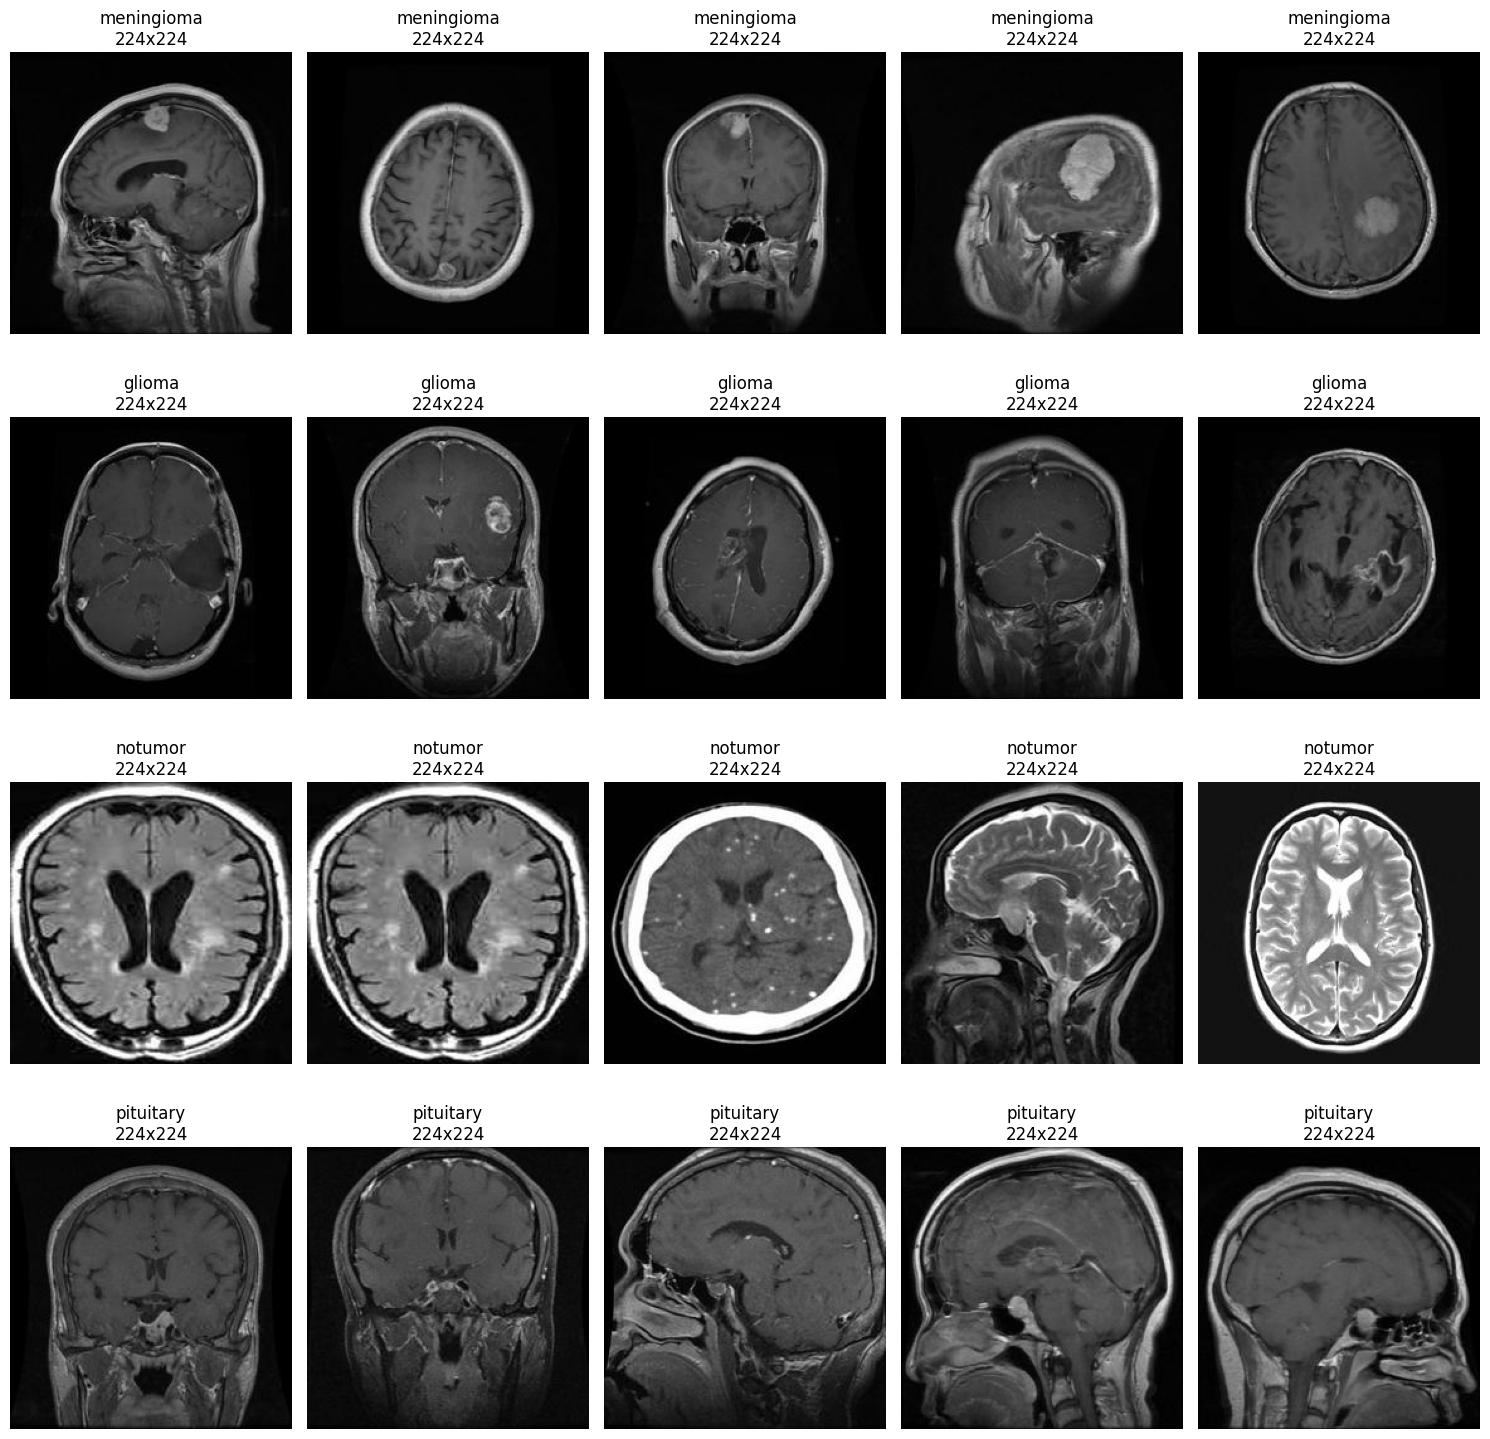

Brain Tumor Classification

Deep Learning / Medical Imaging 2025

A deep learning project using transfer learning with EfficientNet, DenseNet, and MobileNet to classify brain tumors from medical images.

Sample Brain Scan Model Comparison Chart Confusion Matrix Result